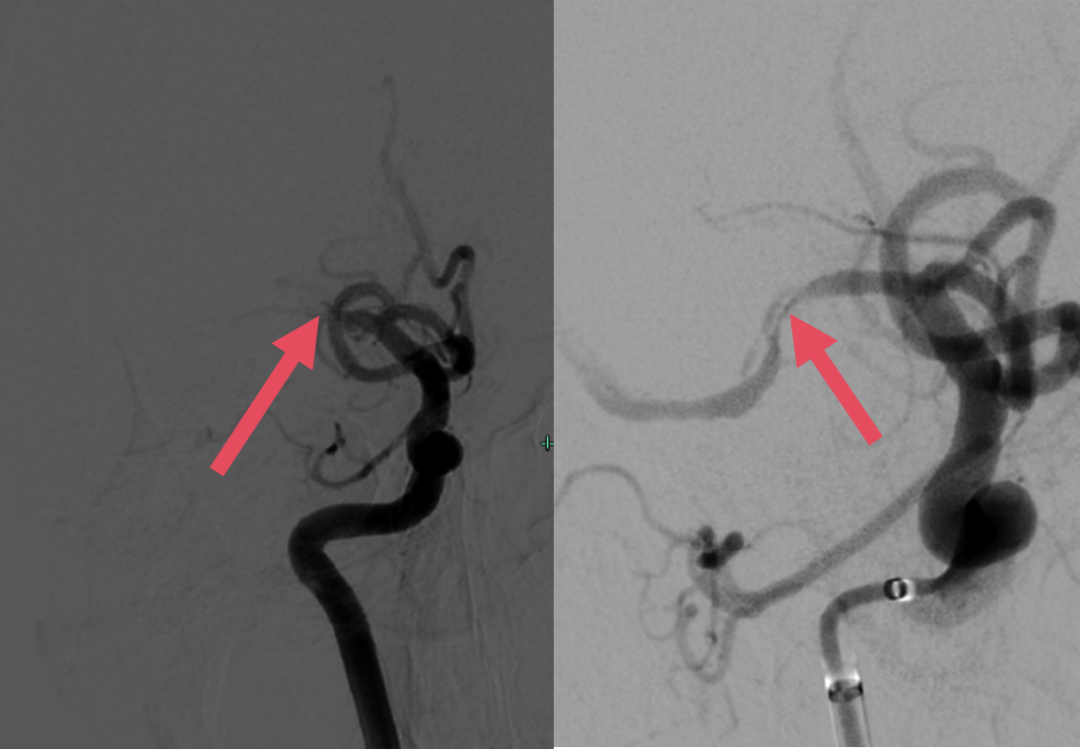

(左图箭头所示为球囊扩张狭窄处,右图箭头所示为球囊扩张狭窄处术后)

“时间就是大脑”,每一分、每一秒都关乎神经功能的存亡。成江主任医师与王胜虎副主任医师高效完成诊断,迅速实施急诊取栓手术。术中发现,小张中风是脑动脉硬化引起的,团队立即采用球囊扩张术,成功实现血管再通,为后续神经功能恢复打下关键基础。

术后,神经介入科、ICU以及康复团队无缝衔接,对小张进行24小时严密监护,密切关注生命体征、神志及瞳孔变化。同时,多学科团队科学制定抗血小板、强化他汀治疗及康复训练方案,促进神经功能迅速恢复,有效预防再梗风险。幸运的是,术后效果显著,小张左侧肢体肌力目前已完全恢复。